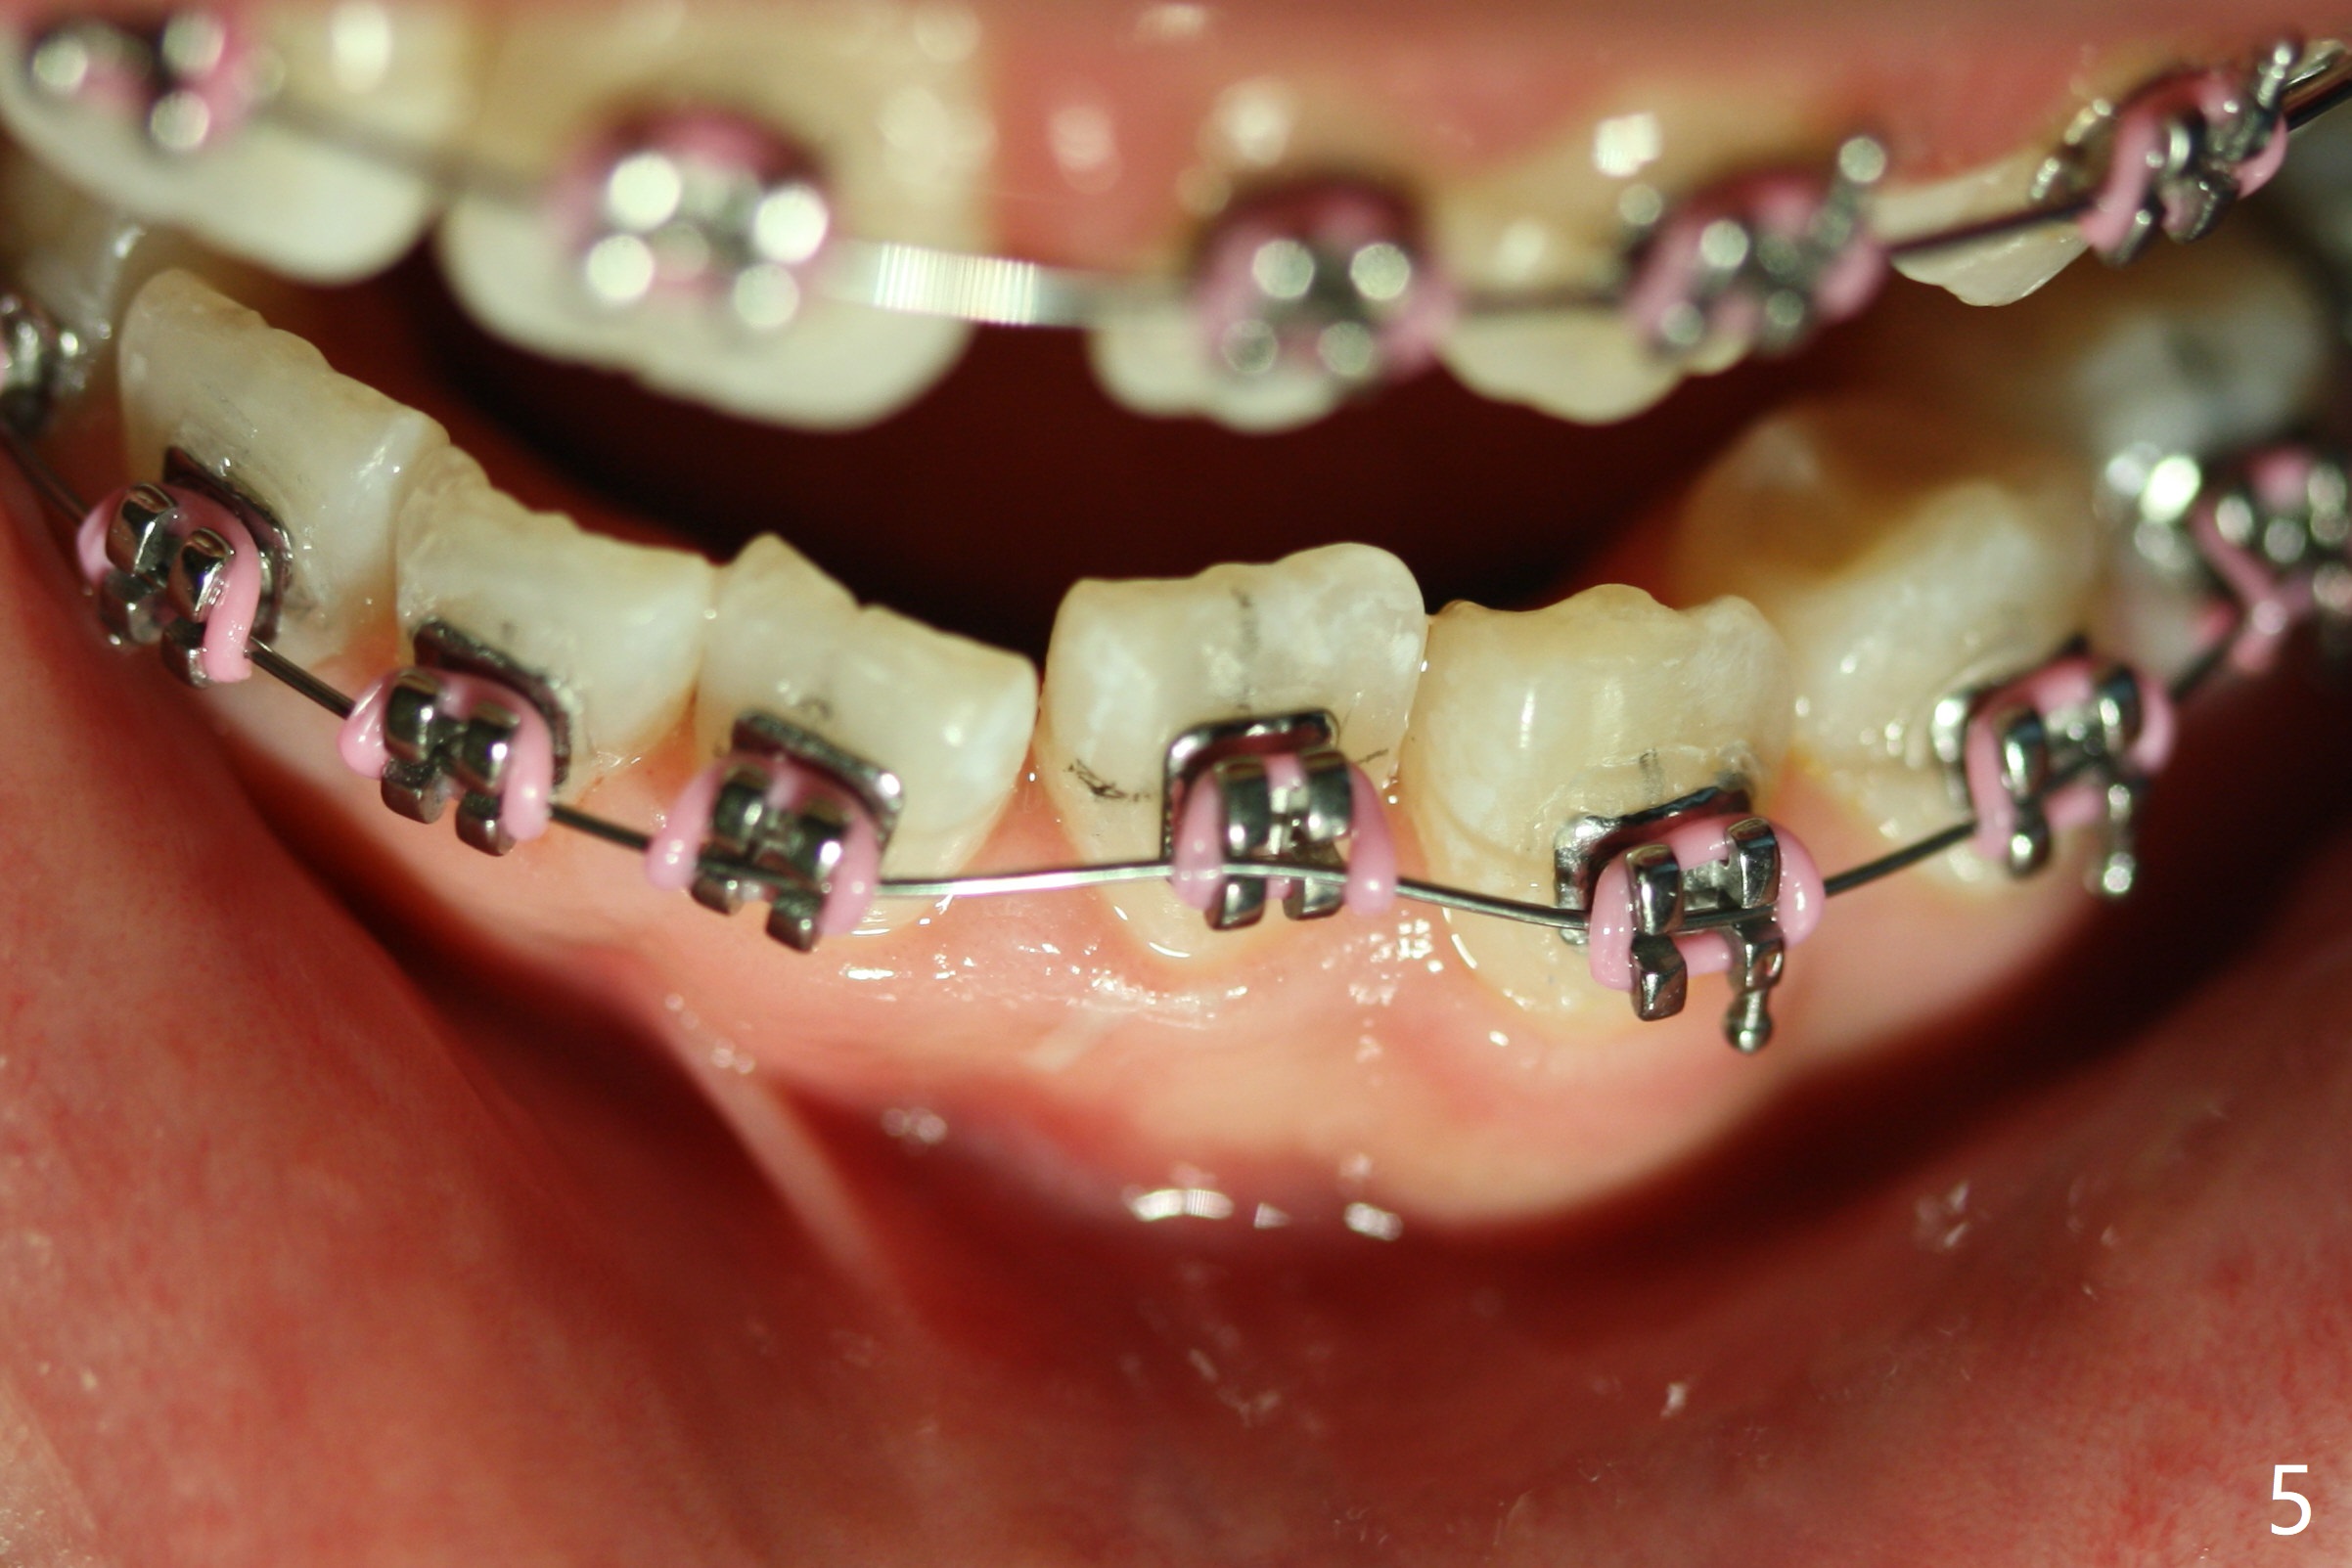

As planned, the peg laterals do not have brackets placed (Fig.2), since their position and shape will be ultimately decided by veneers. Alignment of the lower arch is more severe than that of the upper one, characterized by severe crowding at LR 3 and 4 (Fig.1) and rotation of LL 5 (Fig.3). Oral hygiene does not improve during orthodontic treatment. Impression will be taken prior to debanding. Space is obtained for LL2; brackets are placed at LL2 and 5; 14 niti wire is placed 9 months post banding (Fig.4-6). Orthodontic treatment is terminated prematurely partially due to poor oral hygiene.